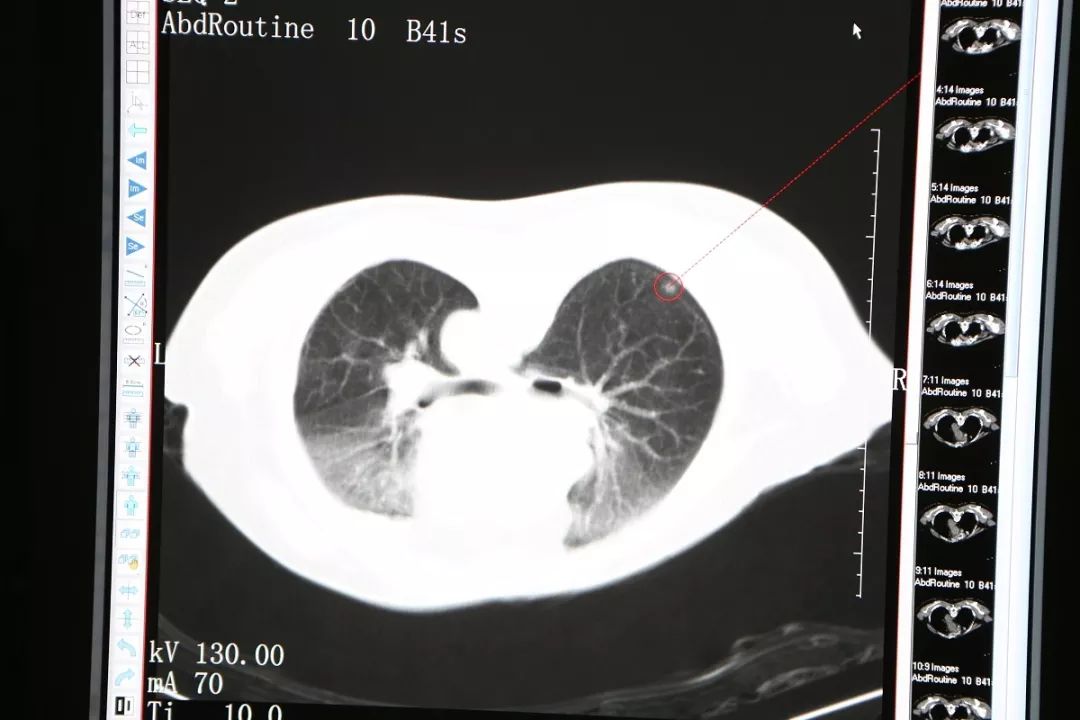

今年69岁的穆阿姨自退休以后就跟着儿子生活在新西兰,并取得了当地绿卡,偶尔返回厦门居住。今年7月她独自返回厦门小住,电视上“双肺毛玻璃”几个字眼触动了她,原来她在今年3月份的体检表上也有这几个字,第二天她去复查胸部CT显示“与2018-03-21CT比较:右肺下叶背段及左肺上叶磨玻璃结节较前相仿”,这时候她体内的磨玻璃影没有变化,她长舒了一口气,但医生建议她继续视察不要放松。到了10月份,她再次到当地医院做CT,发现磨玻璃影虽然没有变大,但是密度增加了,这时候她想起了在电视节目中看到的信息:“密度增加”就要引起关注,如今“密度增加”了表明病症在讯速进展。

肺部磨玻璃样结节是指原发于肺部的均匀含气结节。病灶会沿肺泡生长,并不破坏肺泡构架。但它的密度比正常的肺部组织高,CT影像上面表现为磨玻璃影。典型的磨玻璃样结节多数是癌前病变或者早期肺癌。

穆阿姨来到复大肿瘤医院,迫不及待见了副院长牛立志教授与龙新安医生。龙新安介绍,“这位阿姨右肺下叶背段及左肺上叶磨玻璃结节较前相仿,新见右肺下叶炎性灶,初步诊断为双肺多发结节性质待定,传统手术双肺都有结节,要做两次楔形切除,对患者创伤较大,还有就是传统手术对许多的老年患者容易带来恐惧感。这种状况下只有冷冻消融才有可能把即将形成恶性肿瘤的组织物扼杀在萌芽态势。”得知明天要上手术台,穆阿姨坐卧不安,护士们看出了她的不安,主动与她聊天,她拉着护士的手说“真的很感谢你们,也很不好意思,耽误你们下班了”,护士却说“让你安心,是我们的职责,晚下班算得了什么,不下班都可以”,说着护士紧紧握住她的手,给她以心理安慰。

冷冻消融右肺背段结节

11月26日,穆阿姨被送至微创治疗室在CT引导静脉全麻下行右肺结节氩氦刀冷冻消融术,在实施静脉全麻后,术者将她摆成俯卧位,CT扫描以右肺背段近胸膜处结节为靶区,在CT引导下,用氩气超冷刀经穿刺点准确的穿刺到右肺结节,然后开始实施冷冻。术中通过CT扫描监测冷冻范围和有无并发症的发生,经过两个5分钟的冷冻循环后,CT扫描显示右肺的结节被成功的消融了。CT扫描见冰球覆盖靶区,复温后拔除超冷刀,包扎穿刺点,术中出血2ml,无手术标本,术后麻醉清醒,未诉不适,生命体征平稳。